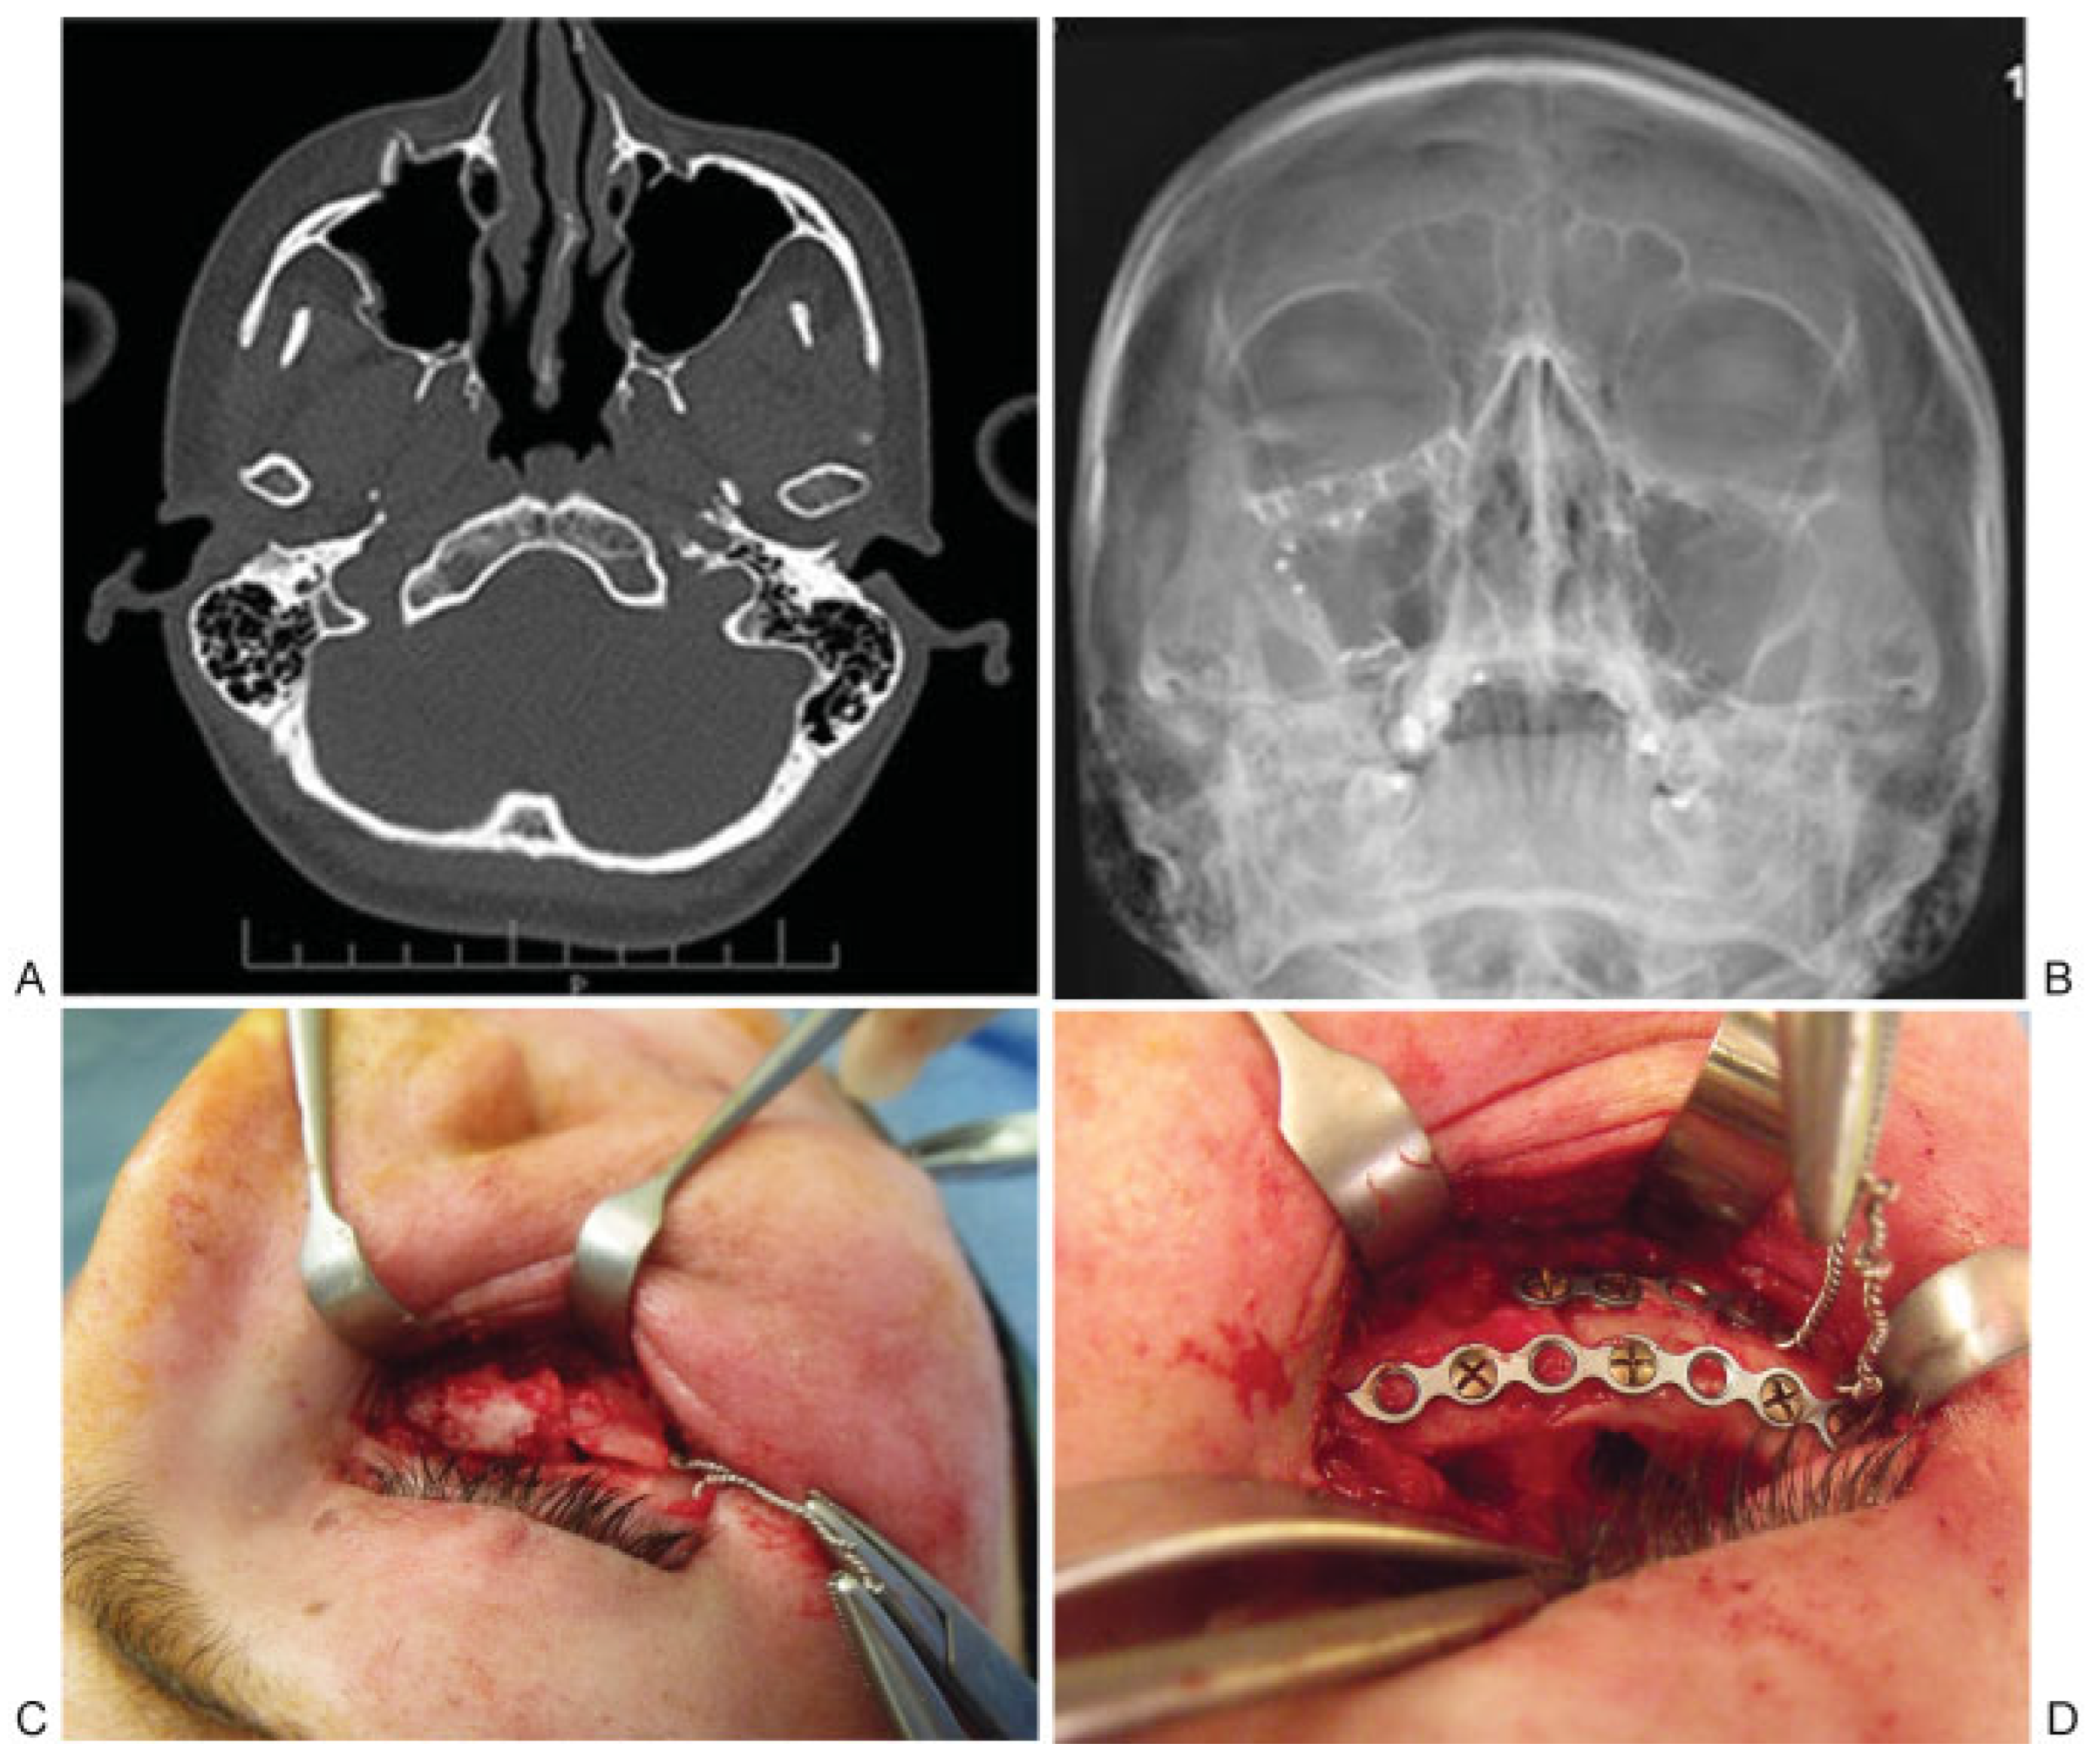

The clinical application of the SWOT technique is shown in a 24-year-old female patient who sustained a right orbitomalar complex fracture involving the lateral and anterior walls of the right maxillary sinus and the right orbital floor as a result of a punch to the face. This was successfully reduced using the SWOT technique alone, 24 days postinjury (Figure 5).

Figure 5.

(A) Preoperative axial section of computed tomography scan showing right orbitomalar complex fractures, (B) postoperative occipitomental radiograph showing reduction of right orbitomalar complex fracture, (C) intraoperative photograph showing comminuted inferior orbital rim and application of SWOT, and (D) intraoperative photograph showing reduction of inferior orbital rim, placement of fixation plates.